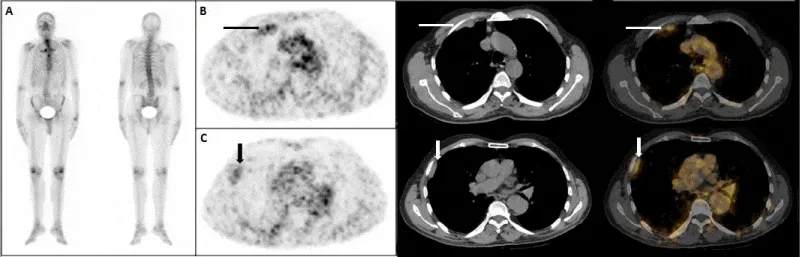

Пэт псма что это

Пэт псма что это 104 фотографий